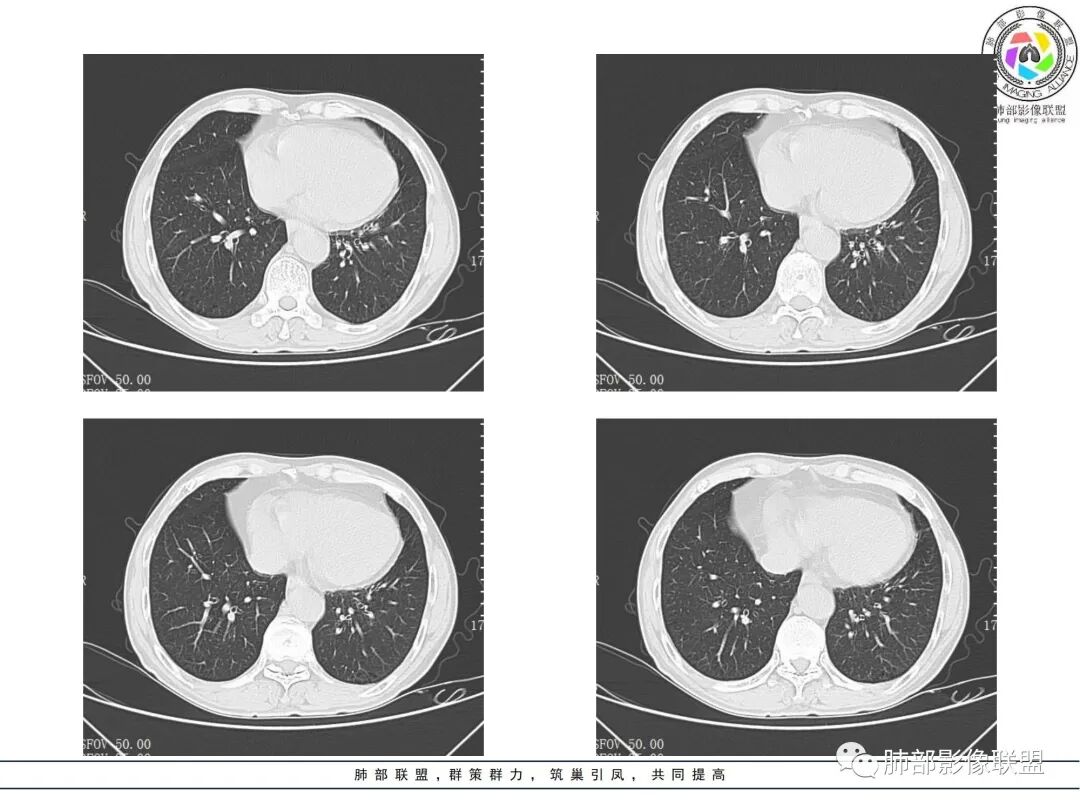

治疗前后对比CT:

放线菌病

1、慢性病程:慢性或亚急性化脓性肉芽肿性炎。

2、跨区域生长:放线菌不受解剖学屏障限制,可经胸膜进入胸腔或其他肺叶,可出现跨叶或累及胸膜、胸壁。

3、脓肿和坏死:局部扩散、多发脓肿、窦道形成,空气悬浮征。